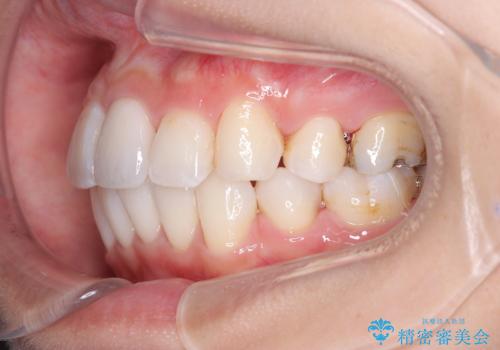

- 口元が出ていることを気にされて来院されました。精密な検査の結果、歯列全体のスペースが不足していることが判明。患者様のご希望である「口元を下げたい」というご要望を叶えるため、上下左右の小臼歯を抜歯し、そのスペースを利用して前歯を奥へ移動させる治療計画を立案しました。また、仕事上、目立つ矯正装置を避けたいというご希望から、上顎に裏側矯正、下顎に表側矯正を組み合わせたハーフリンガル矯正を提案しました。

今回の矯正治療では、口元を大きく下げるため、上下左右の小臼歯を抜歯しました。装置には、上顎は歯の裏側に装着する裏側矯正(舌側矯正)を、下顎は透明で目立ちにくい審美ブラケットを使用するハーフリンガル矯正を選択。これにより、治療中も他人の目を気にすることなく、ストレスなく過ごしていただけました。抜歯によってできたスペースを有効活用し、歯列全体を後方へ移動させることで、口元の突出感を解消。治療の結果、口元がすっきりと整い、自信のある美しい横顔を獲得していただけました。